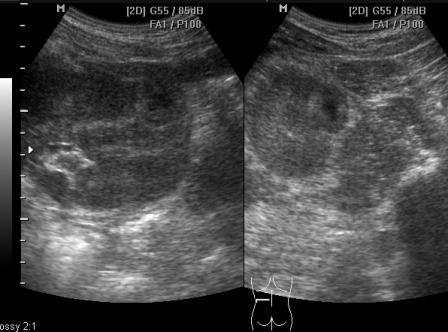

Молодой парень, 23 года, с жалобами на боль в пояснице, повышение температуры тела до 39. В ОАК лейкоцитоз. В ОАМ протеинурия, лейкоцитурия.

УЗИ ОБП: спленомегалия.

УЗИ почек:

Левая почка:

Правая почка:

Похоже на апостематозный пиелонефрит и карбункул левой почки. Сепсис?

Вот и я на 100% была уверена, что это карбункул. Это было почти 3 года назад. Парня перевезли в областную больницу, повторили узи, сделали кт ("нельзя исключить карбункул") и взяли на операцию. В ходе операции выяснилось, что это не карбункул, взяли биопсию. В результате- онкоцитома :shock: Прооперирован.

Онкоцитомы - редкая патология. Обычно в центре д.б. рубец, а здесь - очаг распада (?)

онкоцитома..JPG

онкоцитома..JPG (25.69 КБ) 975 просмотров